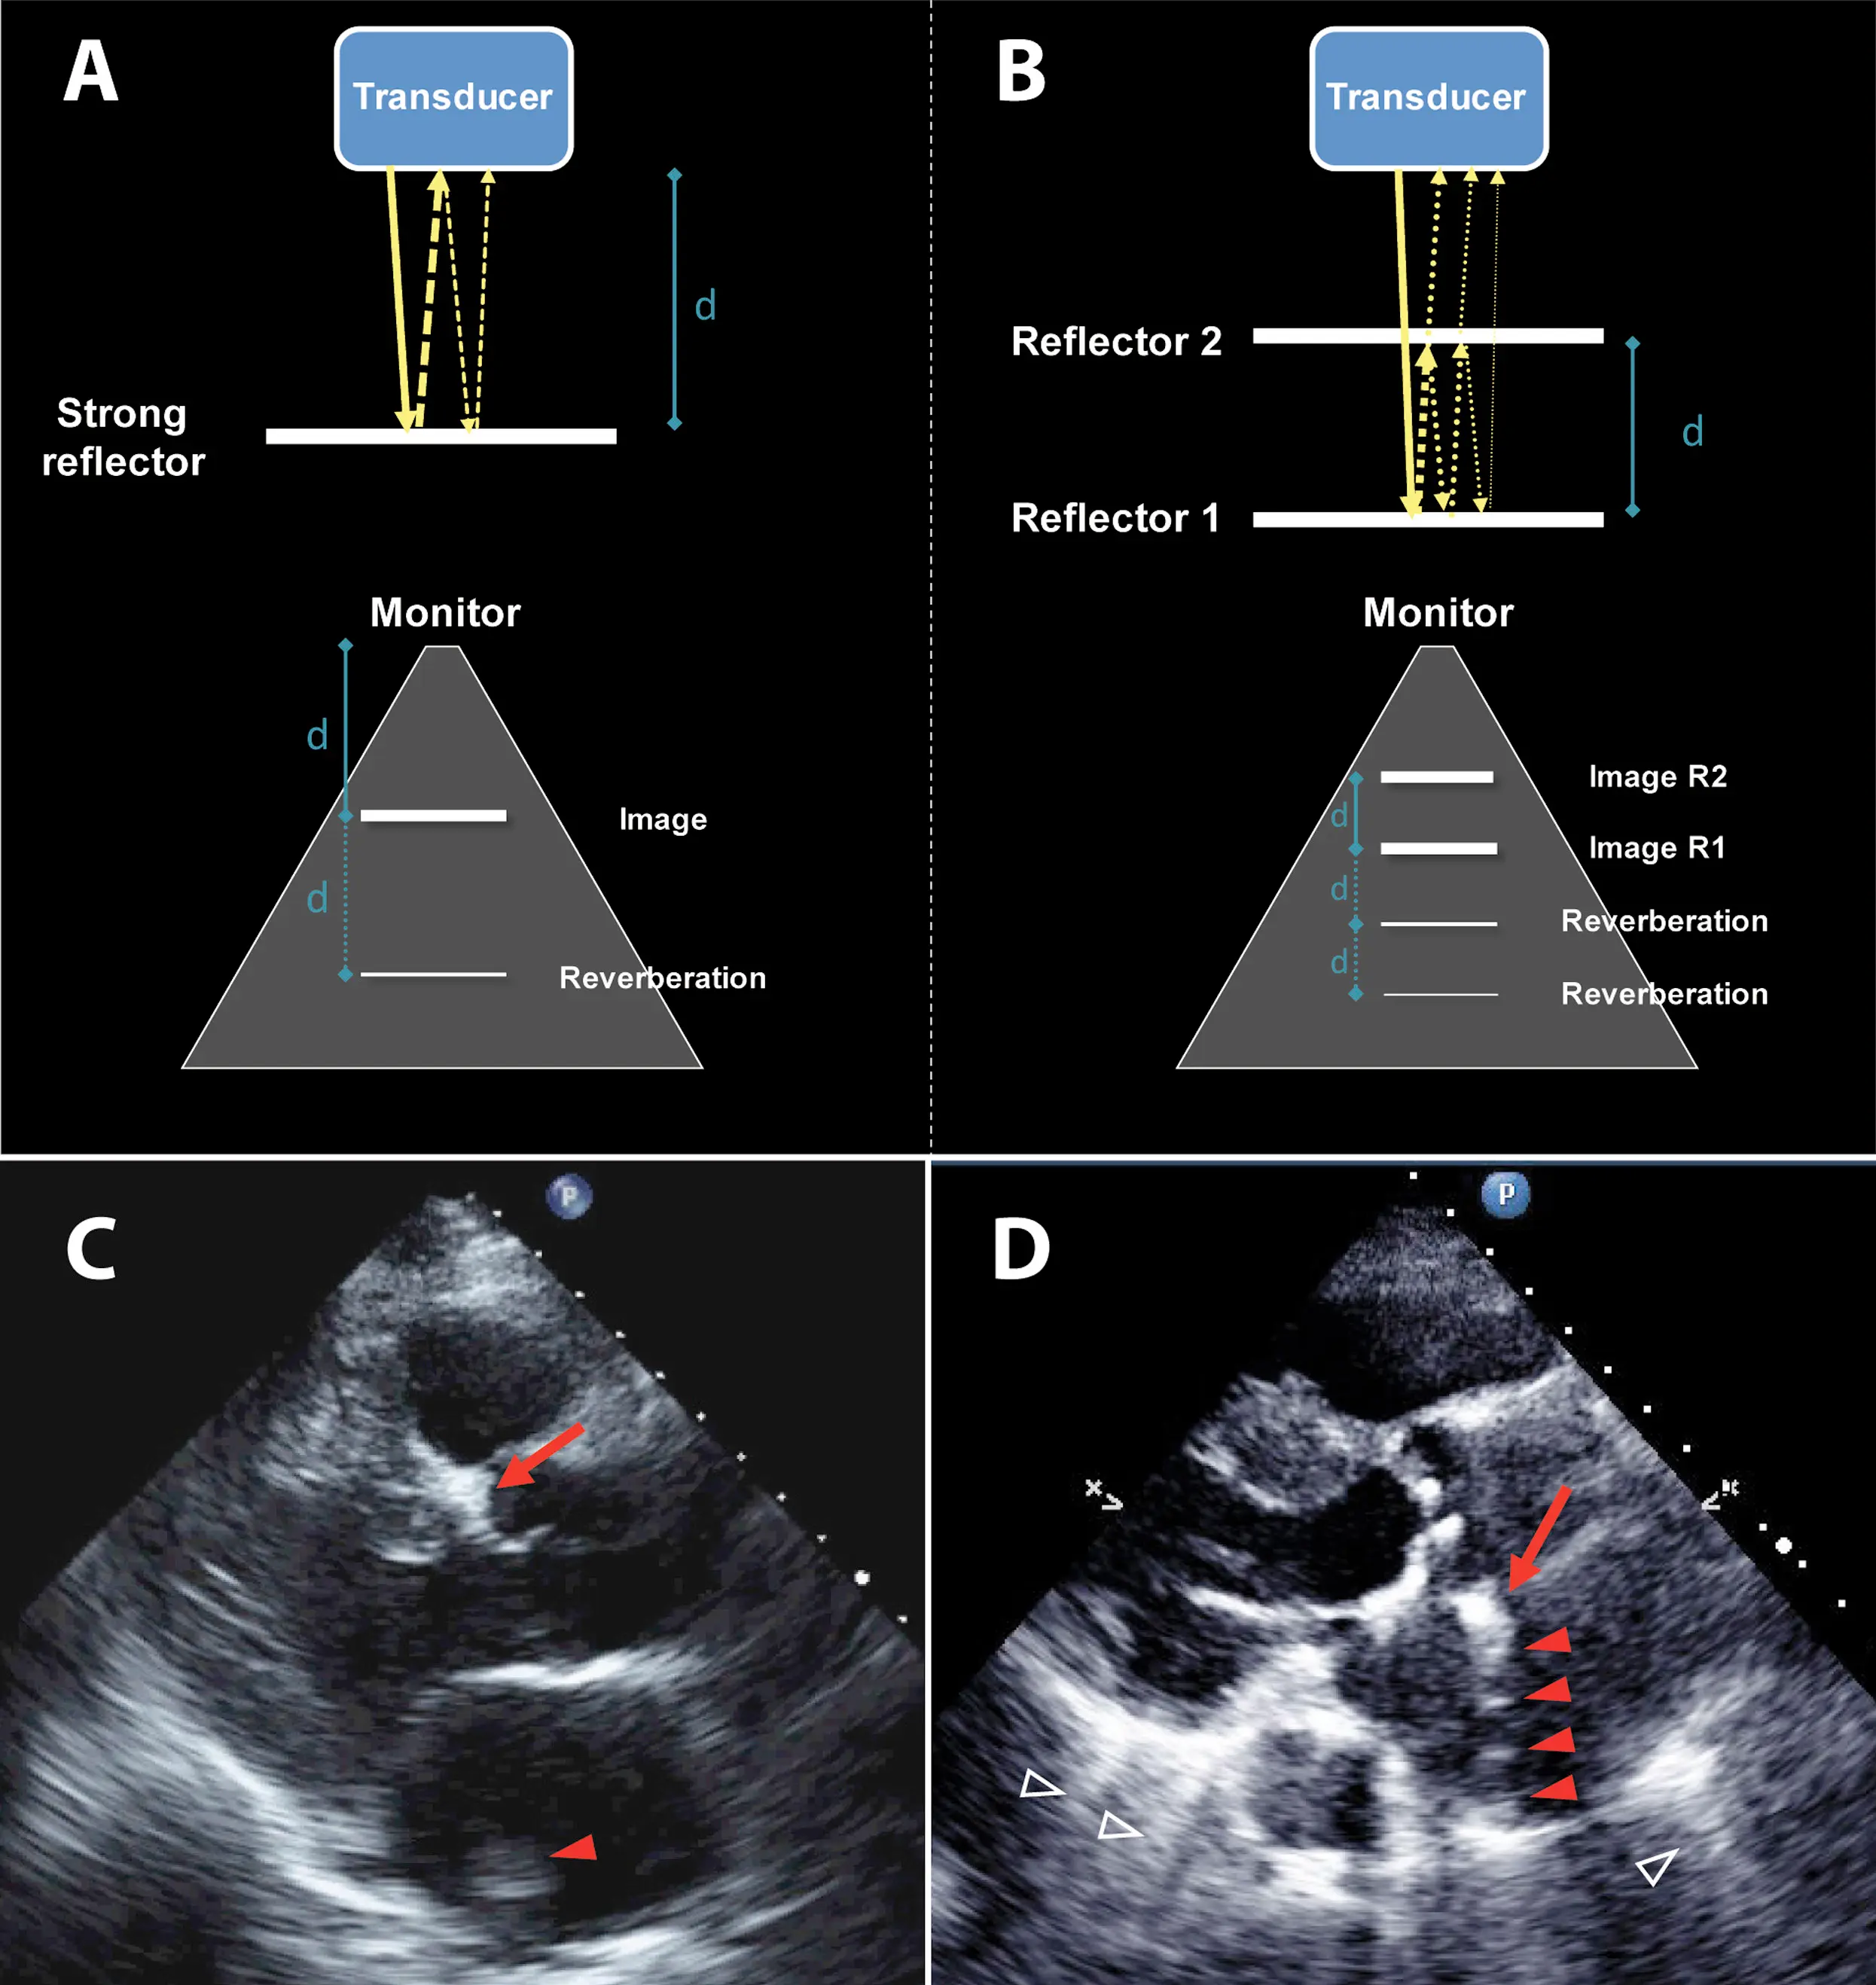

Reverberation

• caused by the ultrasound wave bouncing repeatedly between two strong reflectors, creating multiple, equally spaced, hyperechoic lines that can obscure the true anatomy

• frequently seen when the ultrasound encounters interfaces like the pleura, metallic objects, or implants

• can make these structures appear thicker and deeper than they actually are

• appears as a series of parallel, bright lines that are equally spaced behind the reflective surface